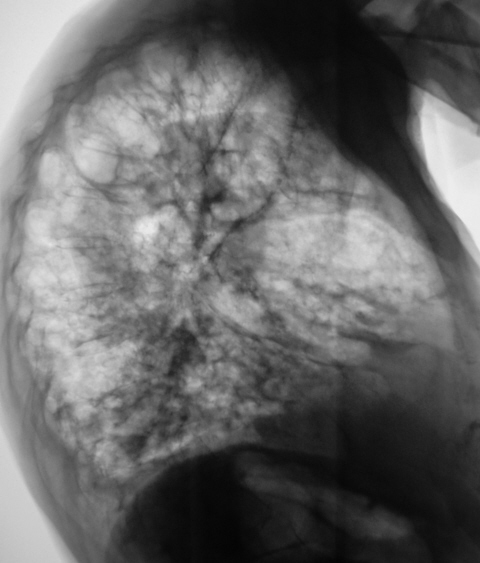

Левое лёгкое.

похожа на синдром тонкостенных полостей

Выглядит ужасно. ПОликистоз? Пациента то что-нибудь беспокоит, кроме одышки?

ПАРАДОКС! Пациентка жалоб не предъявляет. Где-то согласен с Вами. Но как "привязать" картинку левого лёгкого к изменениям в правом лёгком.

фиброзно-буллезная дистрофия? Причина, думаю, кроется в анамнезе, врядли такие изменения развились недавно, быстро и незаметно.

Поликистоз правого легкого, как исход туберкулезного процесса. Необходимы дополнительные клинические и лабораторные данные. Спасибо, тем, кто выслушал.

Валентин Львович! А что вас смушает в левом легком - "плотные" очаги в верхушке?(Просто ТМГ не совсем четкая.) Если так, то могут быть два варианта этиопатогенеза: 1-процесс один с соответствующим исходом, 2- два разных процесса не связанных между собой. Вне зависимости от этого тактика должна быть одна - взять пациента в соответствующую группу диспансерного туб.учета(т.е. 0-а), обследовать (скорее всего данных за активность не получим). А как назвать эту красоту помогут только морфологи,Э только надо ли?

вряд ли это посттуберкулёзные изменения. при таком объёме - полное отсутствие плевральной реакции. но Sergo  прав. но только не 0-А, а 0-Б ГДУ. а дальше фбс, бронхиальный лаваш.

Следовательно, изменения в верхней доле правого лёгкого можно рассматривать, как дизонтогенетические кисты?

Мое мнение это врожденная аномалия развития легочной ткани-поликистоз(так называеммое белое легкое), а учитывая наш менталитет, полудеревенский образ жизни, отсутствие аппаратуры ит.д. на это раньше никто не обращал внимание. Пациент спокойно жил. Я такое видел 3 раза.

Аномалия развития верхней доли правого лёгкого - поликистоз. В нижних отделах правого лёгкого изменения очень похожи на бронхоэктатическую болезнь.